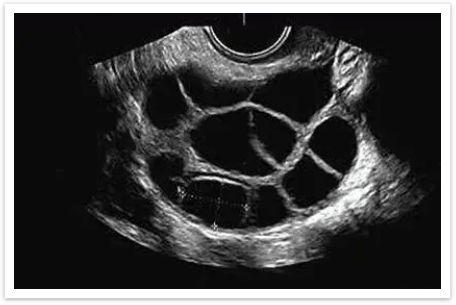

而超声卵泡监测,就像是为备孕安装了一个“GPS导航”,能帮助我们动态、直观地看清这个过程,科学地抓住那稍纵即逝的黄金受孕窗口。

科学备孕,始于对身体的科学认知。卵泡监测并非徒增焦虑,而是以客观数据为备孕提供方向与信心。愿每一位期待新生命的女性,都能循着科学的指引,顺利迎来属于自己的好“孕”。